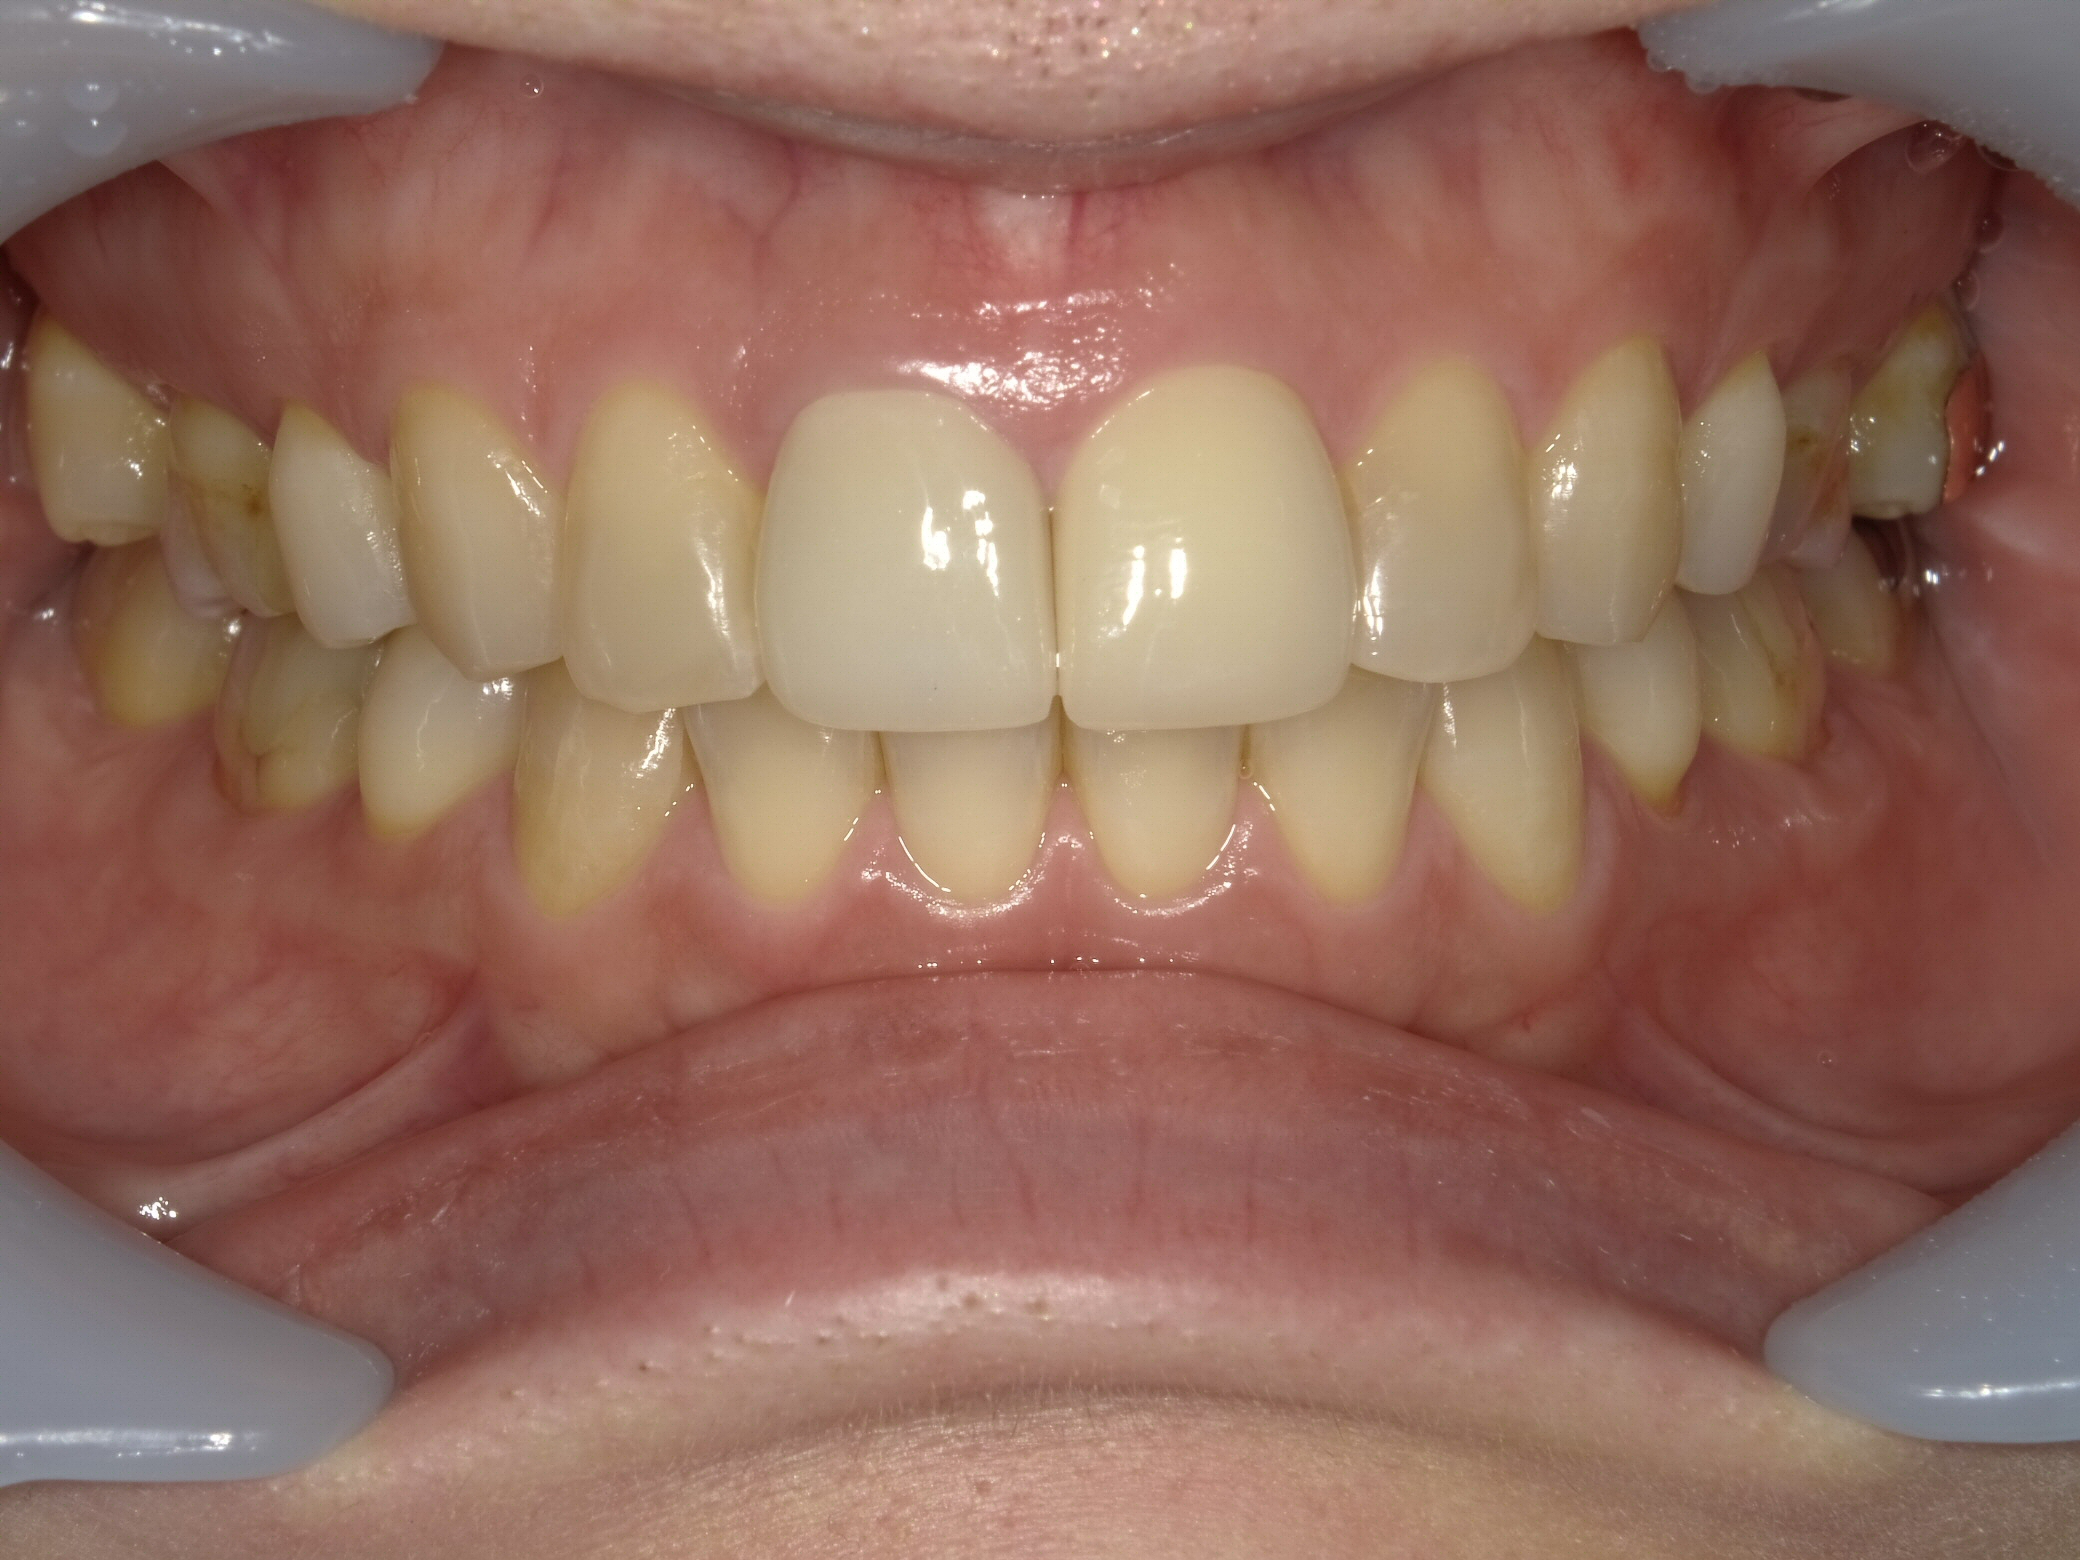

症例1:神経のない歯の変色を改善

「1本だけ色が暗く、笑うときに気になる」というケースです。周りの天然歯に完全に調和させることを目指しました。

【Before】(矢印が神経のない変色歯)全体をホワイトニングしてベースを明るくします。

【After】セラミッククラウン装着。どこを治療したか分からないほど馴染んでいます。

- 治療方法:セラミッククラウン法 + オフィスホワイトニング

- 治療期間:約1ヶ月 / 費用:¥220,000(税込)

- リスク:歯を削る必要があります。